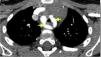

Um rapaz com 2,5 anos apresentou estridor bifásico aos três meses, que agravava com o choro, alimentação e infeções respiratórias altas. Realizou broncofibroscopia (BF) aos cinco meses que diagnosticou traqueomalácia com colapso dinâmico de 80% nos 2/3 inferiores da traqueia. Crescimento normal e sem dificuldade alimentar. Por estridor persistente, a BF aos 21 meses visualizou colapso dinâmico marcado e compressão extrínseca da traqueia. Realizou angiografia por tomografia computorizada (angio‐TC) do tórax, que identificou anel vascular formado por duplo arco aórtico (Figuras 1‐3) responsável por compressão extrínseca sobre a traqueia com franca redução segmentar do seu calibre (Figura 4). Sem outras malformações cardíacas no estudo ecocardiográfico. Aos 23 meses foi submetido a laqueação e divisão do arco mais hipoplásico (anterior esquerdo) por toracotomia. Boa evolução pós‐operatória, mantendo atualmente estridor ligeiro.

Os anéis vasculares representam 1% das cardiopatias congénitas e são a malformação congénita mais frequente com compressão da via aérea. Neste caso a manifestação clínica predominante orientou a sequência de exames de imagem – BF e TC. A combinação de imagens é fundamental na avaliação pré‐operatória. A angio‐TC apresenta vantagens como melhor resolução espacial e temporal, rapidez de aquisição de imagens exigindo apenas sedação/anestesia curta nos doentes não colaborantes, pós‐processamento de imagens com reconstruções tridimensionais e a redução da quantidade de radiação com os equipamentos recentes permite eleger este meio como o preferencial. A avaliação da traqueomalácia ou outro compromisso funcional da via aérea continua a exigir a realização de videobroncoscopia.